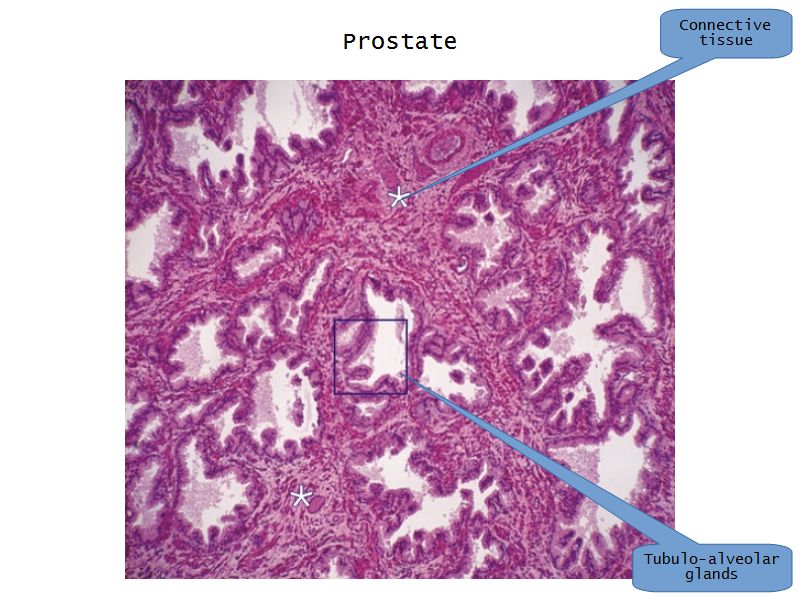

Prostate

Slide 80Prostate

- Surrounds urethra

- Largest accessory gland

- 30 - 50 branched tubuloalveolar glands

- Via excretory ducts

- Into urethra

Glands

- 3 concentric layers

- Around urethra

- Mucosal

- Submucosal

- Main

Capsule

- Fibroelastic capsule containing smooth muscle

- Divides into lobes

Concretions

- Sometimes in lumen

- Calcified

- Increase with age

Epithelium

- Simple columnar or

- Pseudostratified columnar

- Surrounded fibroelastic CT

- CT with rich vascular supply